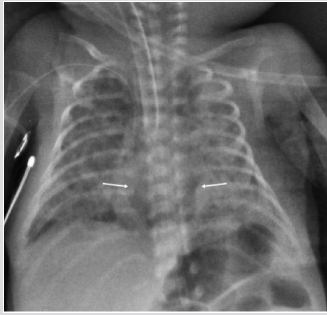

A female was born at 39th week of pregnancy by a regular vaginal delivery. Her body weight was 3100 g. Prenatal US was normal. At two days old, she presented clinical signs of respiratory depression who required supplemental oxygen. Chest X-ray showed a wide radiolucent area over the mediastinum (Figure 2). Chest CT was performed the same day. A large multiloculated mass was detected in the anterior mediastinum, with the thymus compressed upwards. There was evidence of pneumothorax without signs of PIE (Figure 2). A drainage was positioned and the case was completely resolved.

Figure 2: Female two days old. A) Chest X ray. Huge round median lucency (white open arrows) displacing the thymus cranially (white arrow).

A male born at 30th week of pregnancy, of 1100-g, developed respiratory distress after delivery and chest X-ray showed the signs of a Respiratory Distress Syndrome (RDS). The baby was intubated. During the second day of life, a typical PIE was detected, on the third day of life a large retro cardiac air collection was identified. The lucency was on the midline (Figure 3). CT was performed to localize the large air collection that appeared oblong, well circumscribed, and crossing the midline. There was shift of the mediastinal structures anteriorly. The air-filled mass was interpreted either an infra-azygous pneumomediastinum or an air collection in the pulmonary ligament [5]. Over the following week, the extra ventilatory air collections is gradually resorbed: the large midline gas collection became smaller and didn’t shift laterally suggesting an infra azygous pneumomediastinum [6]. During the subsequent week, the median gas collection has shrunk but it not shifting sideways (Figure 3).

Figure 3: Preterm male two days old. A) Chest X ray (AP View). Median oblong well limited transparency (arrow). Bilateral PIE.